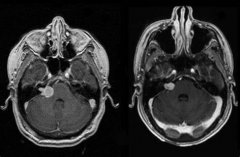

尽管 听神经瘤 是良性的,但它们会严重影响生活质量。单侧听力...

听神经瘤 是耳蜗或前庭神经增厚的情况。它可能导致听力丧失和...